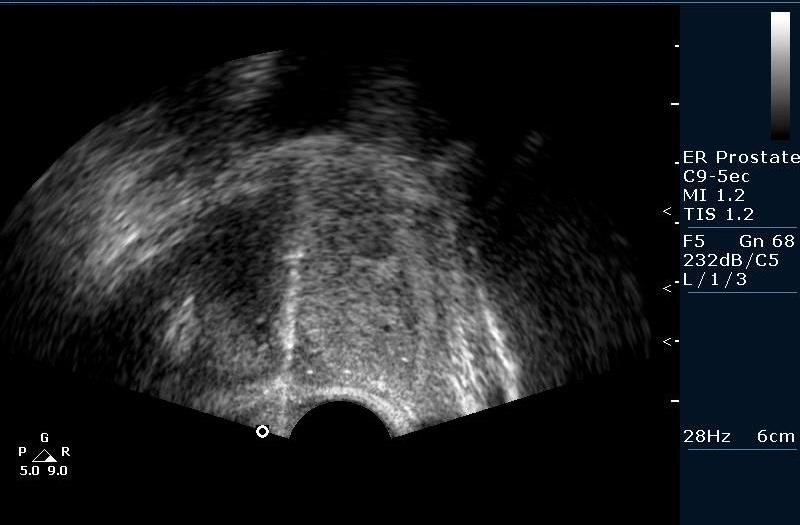

Биопсия предстательной железы под контролем Ультразвуковой визуализации. Рутинная практика в нашем отделении pадиологии, выполняется практически всем пациентам с повышенным уровнем ПСА (естественно, учитывая результаты осмотра урологов).

Предстательная железа